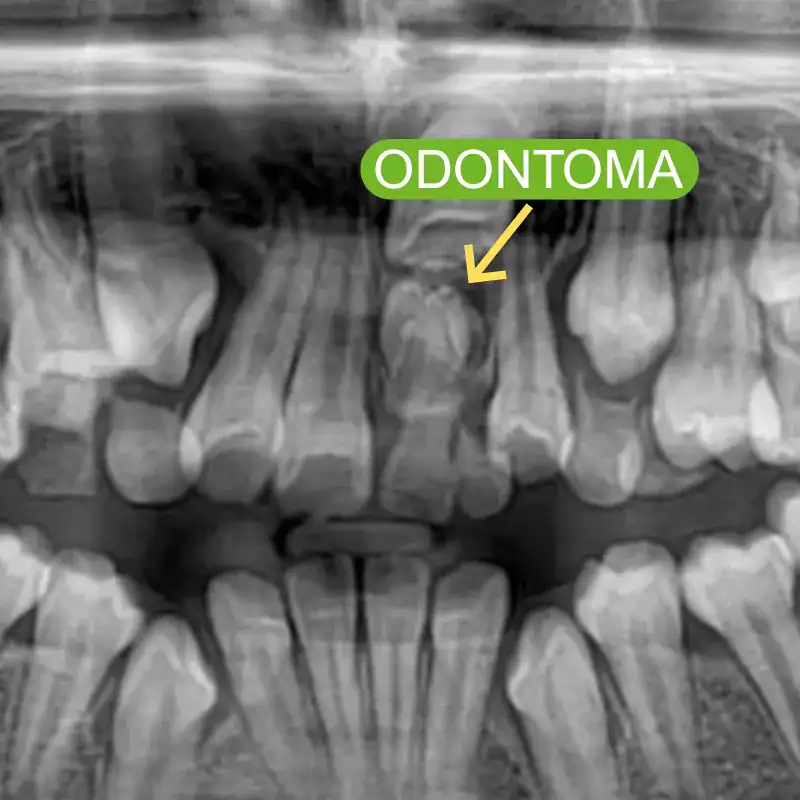

Tratamiento de quistes y odontomas

Los quistes son bolsas de contenido líquido que pueden formarse en los tejidos, y los odontomas son crecimientos benignos compuestos por tejido dental.

Ambos pueden afectar el desarrollo dental y óseo.

La cirugía se realiza para eliminar estas formaciones de manera segura, ayudando a prevenir complicaciones y permitiendo un desarrollo adecuado de los dientes y los huesos